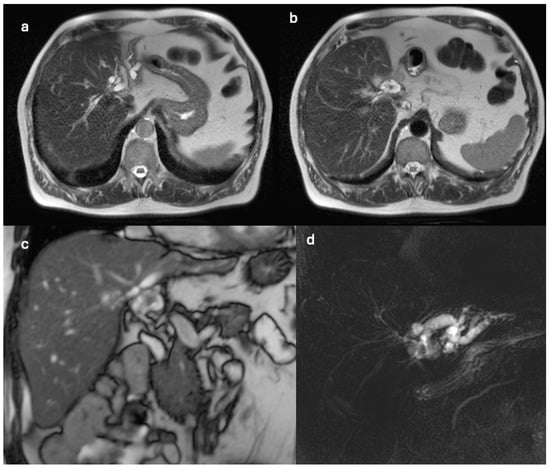

| Feature | Case 1 | Case 2 |

| Patient Demographics | 60-year-old Caucasian male | 28-year-old Caucasian female |

| Clinical Presentation | Incidental discovery of an 8 × 8 × 9 cm hepatic cyst | Presented with dyspnea, vomiting, jaundice, fever |

| Initial Diagnosis | Suspected hydatid cyst | Simple cyst, later adenocarcinoma with metastases |

| Diagnostic Methods | MRI, MRCP, ERCP, histopathological examination | CT, MRI, laparoscopic liver biopsy, histopathological examination |

| Tumor Characteristics | Large cystic mass, thin walls, internal septa, papillary projections, enhancing solid components | Large lesion in left hepatic lobe, hyperintensity in T2-weighted images, restricted diffusion, contrast enhancement |

| Treatment | Cyst resection, cholecystectomy | Thrombectomy, chemotherapy, supportive care |

| Surgical Findings | Partially exophytic floating soft mass | Extensive intrahepatic metastases, vascular involvement |

| Histopathological Findings | IPNB with foci of adenocarcinoma, oncocytic appearance, varying degrees of dysplasia, mucus within cyst | Adenocarcinoma with papillary clear cell and mucinous appearance, gland ectasis, cystic or pseudocystic aspects |

| Follow-up and Outcome | Initial recurrence-free survival for 8 years, recurrence treated with left hepatectomy, patient alive at 33 months post-second surgery | Disease progression despite aggressive management, patient died from hepatic failure |